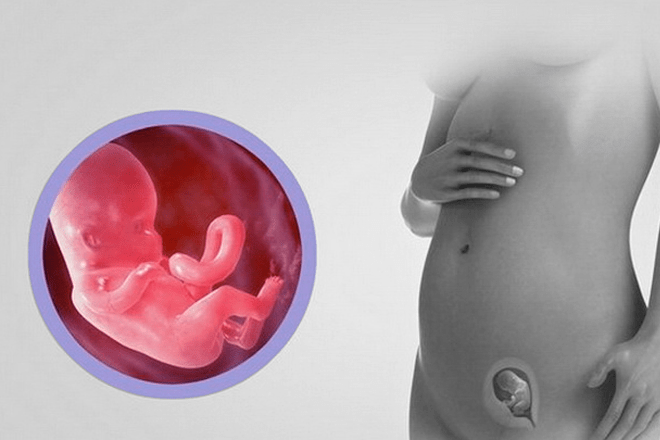

Развитие зародыша на 12 неделе: визуальный обзор